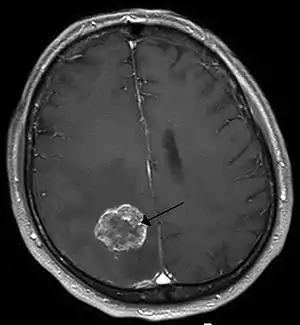

- Brain tumor

- Cavernoma